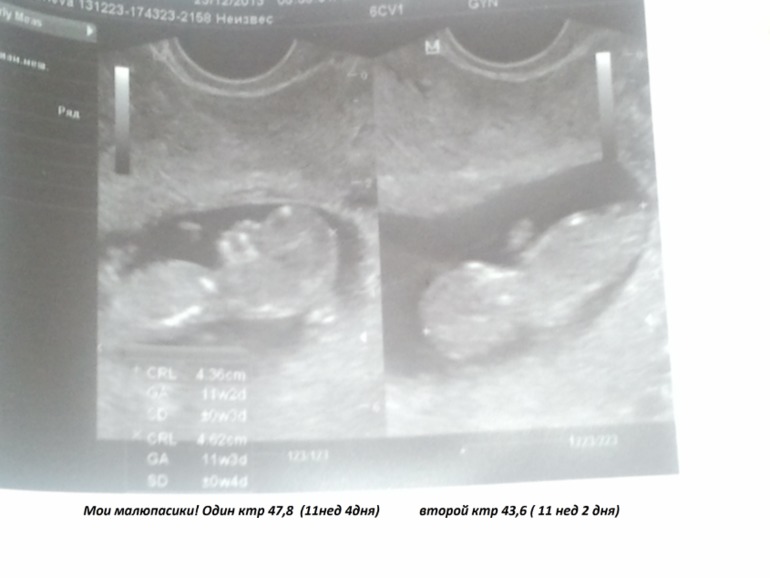

Я буду мамой двойняшек! Принимаем в наши рядыНу вот и я стала счастливой обладательницей двойного счастья. И так коротко о нас: нам 12 недель, по результатам узи подозрение на монохориальную биамниатическую двойню. Малышики практически одинаковые в развитие с разницей в 2-а дня. Ктр первого 47,8 (11 н 4 дня) второго 43,6 ( 11нед 2 дня). Узи делала 23.12.2013. Из минусов: детки прикрепились по задней стенке полностью перекрыв внутренний зев. Ну а в остальном все хорошо.

Ну а вот и мои пупсята.